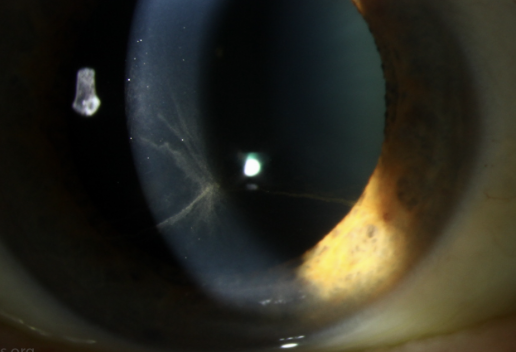

Filamentary Keratitis: caused by chronic corneal inflammation usually from dry eyes -> degenerated epithelial cells + mucous attached to create the filaments. Assocuated with dry eye, ocular infla, CL wear.

Plan:

debride filaments with Q-Tips and anesthetic

PFAT 6-8x a day + lubricating gel + punctal plugs

Acetylcysteine 10% QID (Dissolve mucus plaques)

RTC 1-4 weeks. Consider BCL if not better